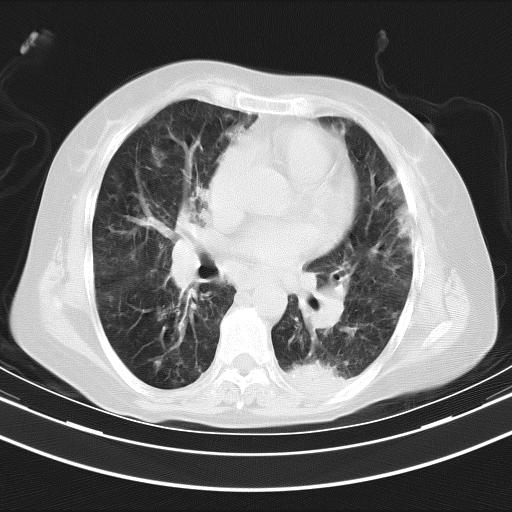

老年女性,嗜睡3天,意识模糊。轻咳,无发热。

两肺慢支炎伴感染,左侧胸腔积液。纵膈及双侧肺门淋巴结肿大建议复查。

双肺多发淡片影,毛玻璃影,,支持支气管肺炎,,建议血气找原因,,嗜睡是否肺性脑病?有没有慢支病史?

双肺炎症,建议抗炎治疗后复查,见过几个老年肺炎病例,没有发烧、咳嗽症状,直接以昏迷就诊。

1)两肺感染性病变;建议抗炎治疗后复查。2)纵隔淋巴结肿大。3)左侧胸腔积液。